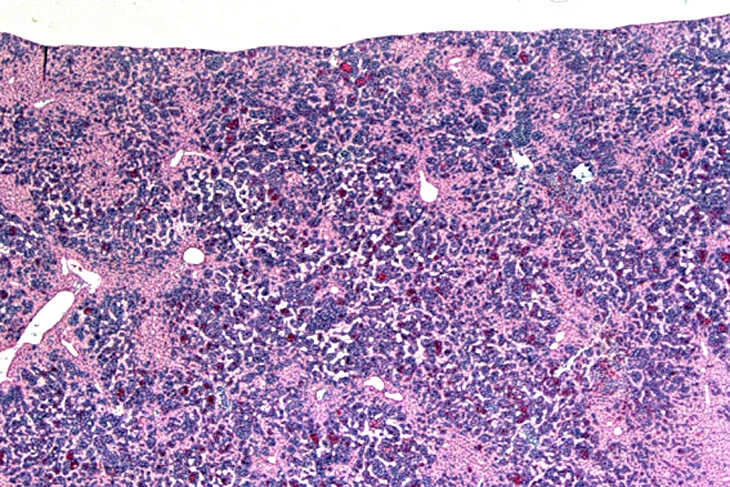

Erythroleukemia is a spontaneous hematopoietic neoplasm of Tg.AC mice characterized by marked hepatomegaly. The affected liver is infiltrated by metarubricytes and less differentiated erythroid precursors.

Low magnification of erythroleukemic infiltrates in the liver.